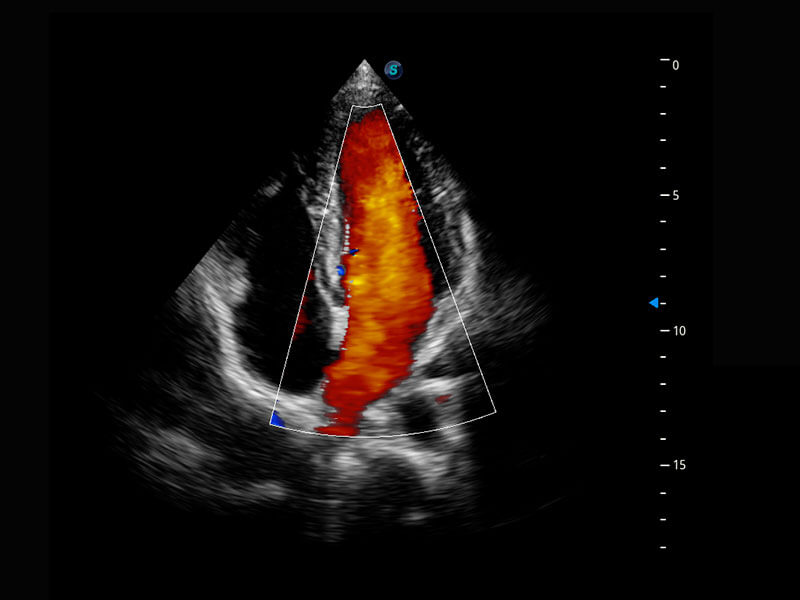

新生儿心脏